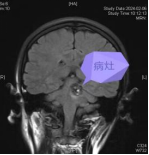

33岁的陈女士(化名)近来总觉得右半边身体麻木无力,走路不稳、头痛头晕,来到我院神经医学中心求诊。通过磁共振检查,发现其脑干偏左侧,有个海绵状血管瘤,同时还伴有出血。

术前检查:海绵状血管瘤处于脑干偏左侧